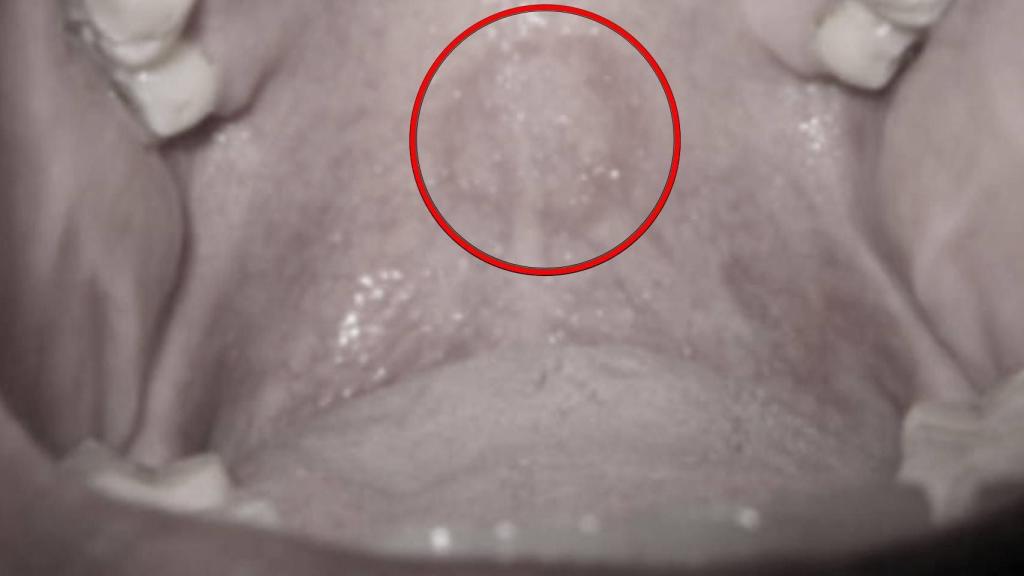

El eritema apreciable en el paladar blando del paciente.

Este extraño caso comienza del modo más anodino: con una visita rutinaria al dentista. El protagonista es un hombre de 47 años que acudió a la Escuela de Odontología de la Universidad de Morelos en Monterrey, México, porque había perdido uno de sus empastes. Cuando los especialistas procedieron a examinar su boca, descubrieron algo inusual en el paladar blando, una marca circular roja.

Este tipo de lesiones se conocen como eritemas y apuntan a una congestión de los vasos sanguíneos. Pero el paciente, según explicó, no era consciente de haber sufrido herida alguna en esa zona. Los dentistas continuaron inquiriendo sobre sus hábitos de vida para tratar de dar con el motivo y el hombre terminó explicando que practicaba sexo oral con frecuencia. Felaciones, concretamente.

La última de estas actividades sexuales había tenido lugar apenas tres días antes de acudir al dentista, y también había involucrado el consumo de cocaína y marihuana, por lo que podría haberse lastimado sin darse cuenta por un exceso de fogosidad. "El contacto del paladar con el glande puede provocar un hematoma por traumatismo" - explica el equipo del doctor Luis Alberto Méndez en el artículo que redactaron para describir el caso y que publica BMJ Case Reports.

Otro factor contribuyó al desarrollo del eritema, explican los especialistas, y es que la succión del pene habría dilatado las venas de la boca y facilitado la hinchazón. Con todo, la lesión era de carácter benigno, y en un chequeo posterior realizado tres días después se comprobó que había desaparecido.